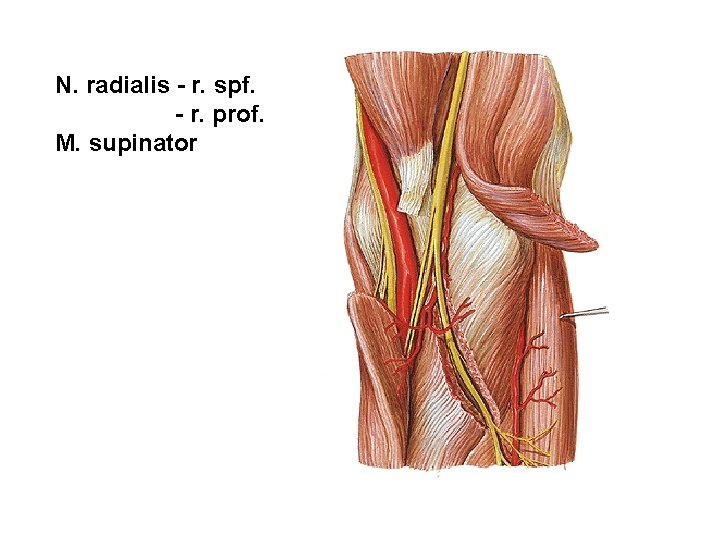

N. radialis - r. spf. - r. prof. M. supinator